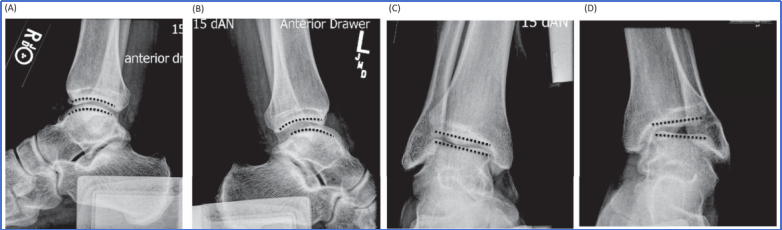

应力X线在慢性外侧踝关节不稳(CLAI)的诊断中应用广泛,可通过施加前向拉力(前抽屉应力)或内翻力(内翻应力),评估距骨的前向移位程度和倾斜角度,辅助判断外侧韧带(如前距腓韧带、跟腓韧带)的损伤情况。

图4 前抽屉应力位:显示患侧(图B)距骨相对于胫骨的异常前移超过10毫米,而健侧(图A)无此现象。距骨倾斜位:显示患侧(图D)距骨相对于胫骨的异常倾斜角度超过10度,而健侧(图C)无此现象。黑色虚线代表胫骨远端与距骨穹顶的踝关节线。